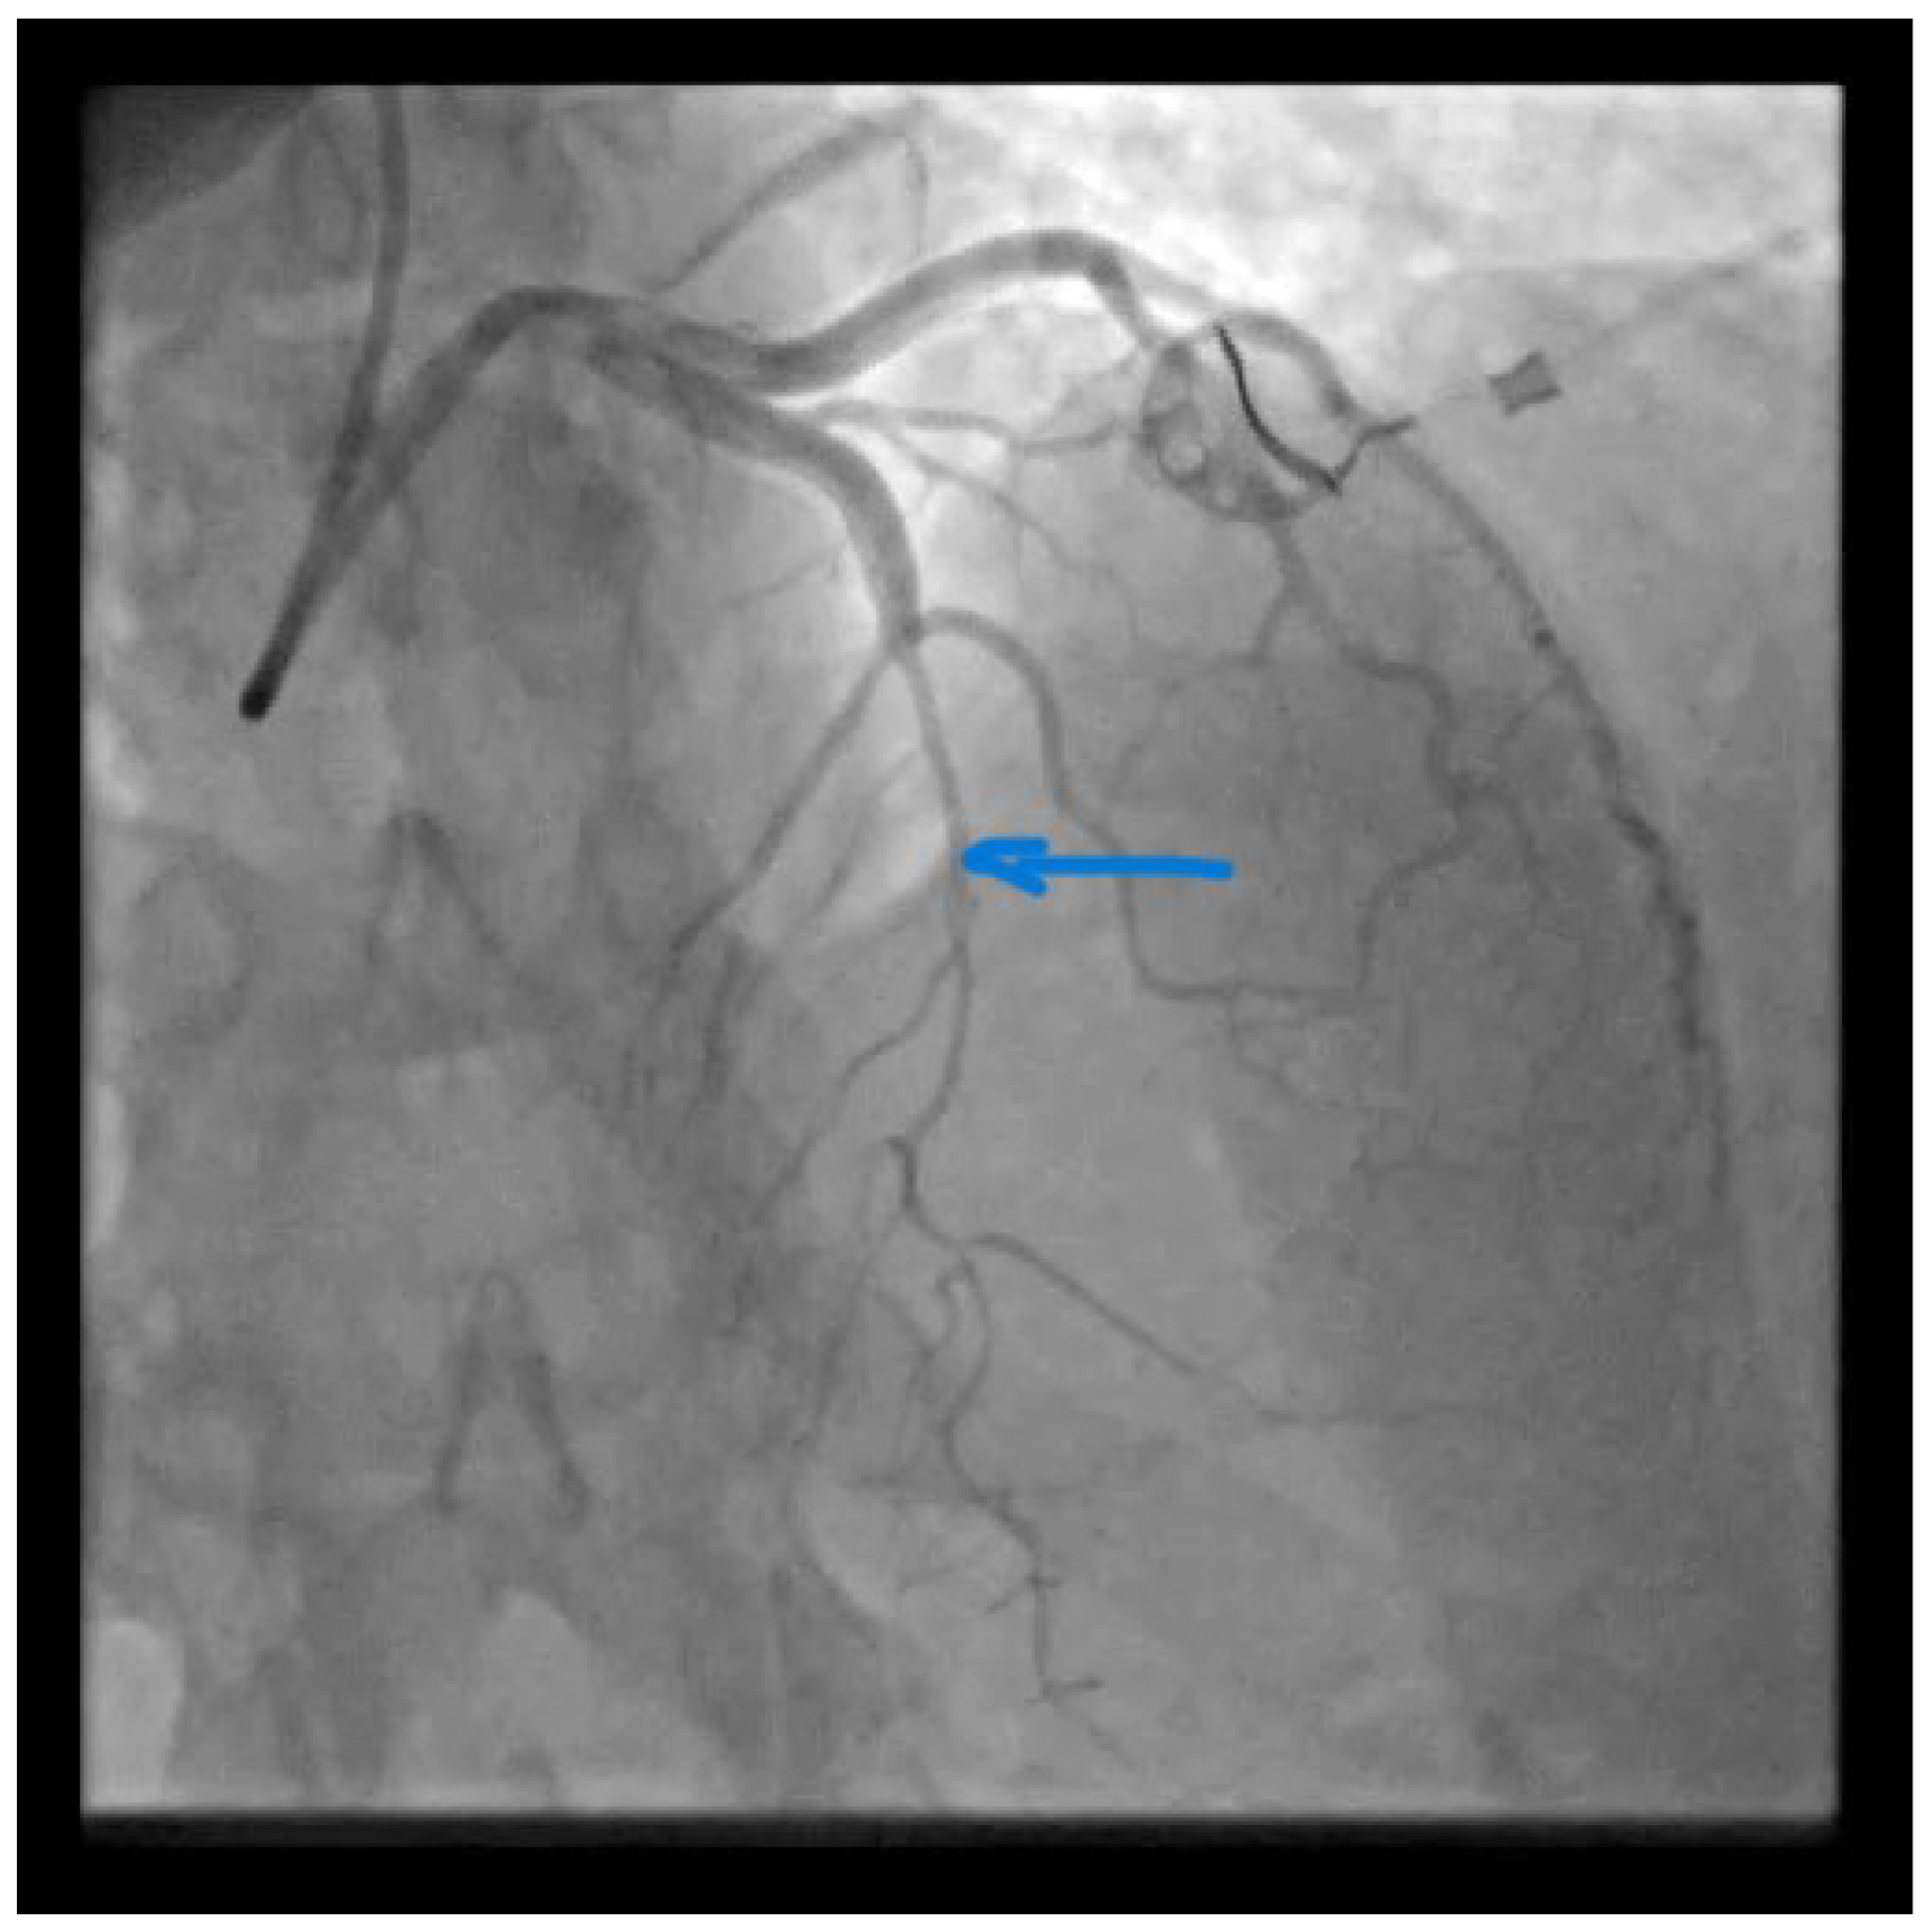

Catheterization of the coronary artery showed spontaneous type 2B coronary artery dissection (SCAD) with thrombolysis in myocardial infarction (TIMI) with flow grade 2 of the left anterior descendent (LAD) coronary artery located in the medial distal segments (blue arrow) where stenosis extends to the end of the vessel (Video S1). SCAD is defined as a nonatherosclerotic or iatrogenic separation of the coronary arterial tunics with a non-traumatic cause, secondary to vasa vasorum hemorrhage or intimal tear, which creates a false lumen, coronary compression, and downstream myocardial ischemia [1]. The primarily affected demographic groups are young-to-middle-aged women [1]. This can sometimes be an unrecognized condition. SCAD can cause acute myocardial infarction (AMI) and sudden cardiac death [2,3]. A previously healthy 42-year-old woman presented to the emergency department with a complaint of gradually squeezing chest pain in rest which lasted for 2.5 h. She had also noticed vomitus and an increased blood pressure value of of 170/120 mmHg. She was admitted to the Cardiology Department at the University Clinical Center of Serbia. No previous diseases were found in her medical history. She underwent five normal deliveries and one spontaneous abortion. The last delivery was eight years ago. She did not use any hormonal therapy. No special family history was reported. In admission to the Coronary Care Unit, she was hemodynamically stable and without signs of heart failure. Her blood pressure was 120/80 mmHg and her heart rate was 98 bpm.